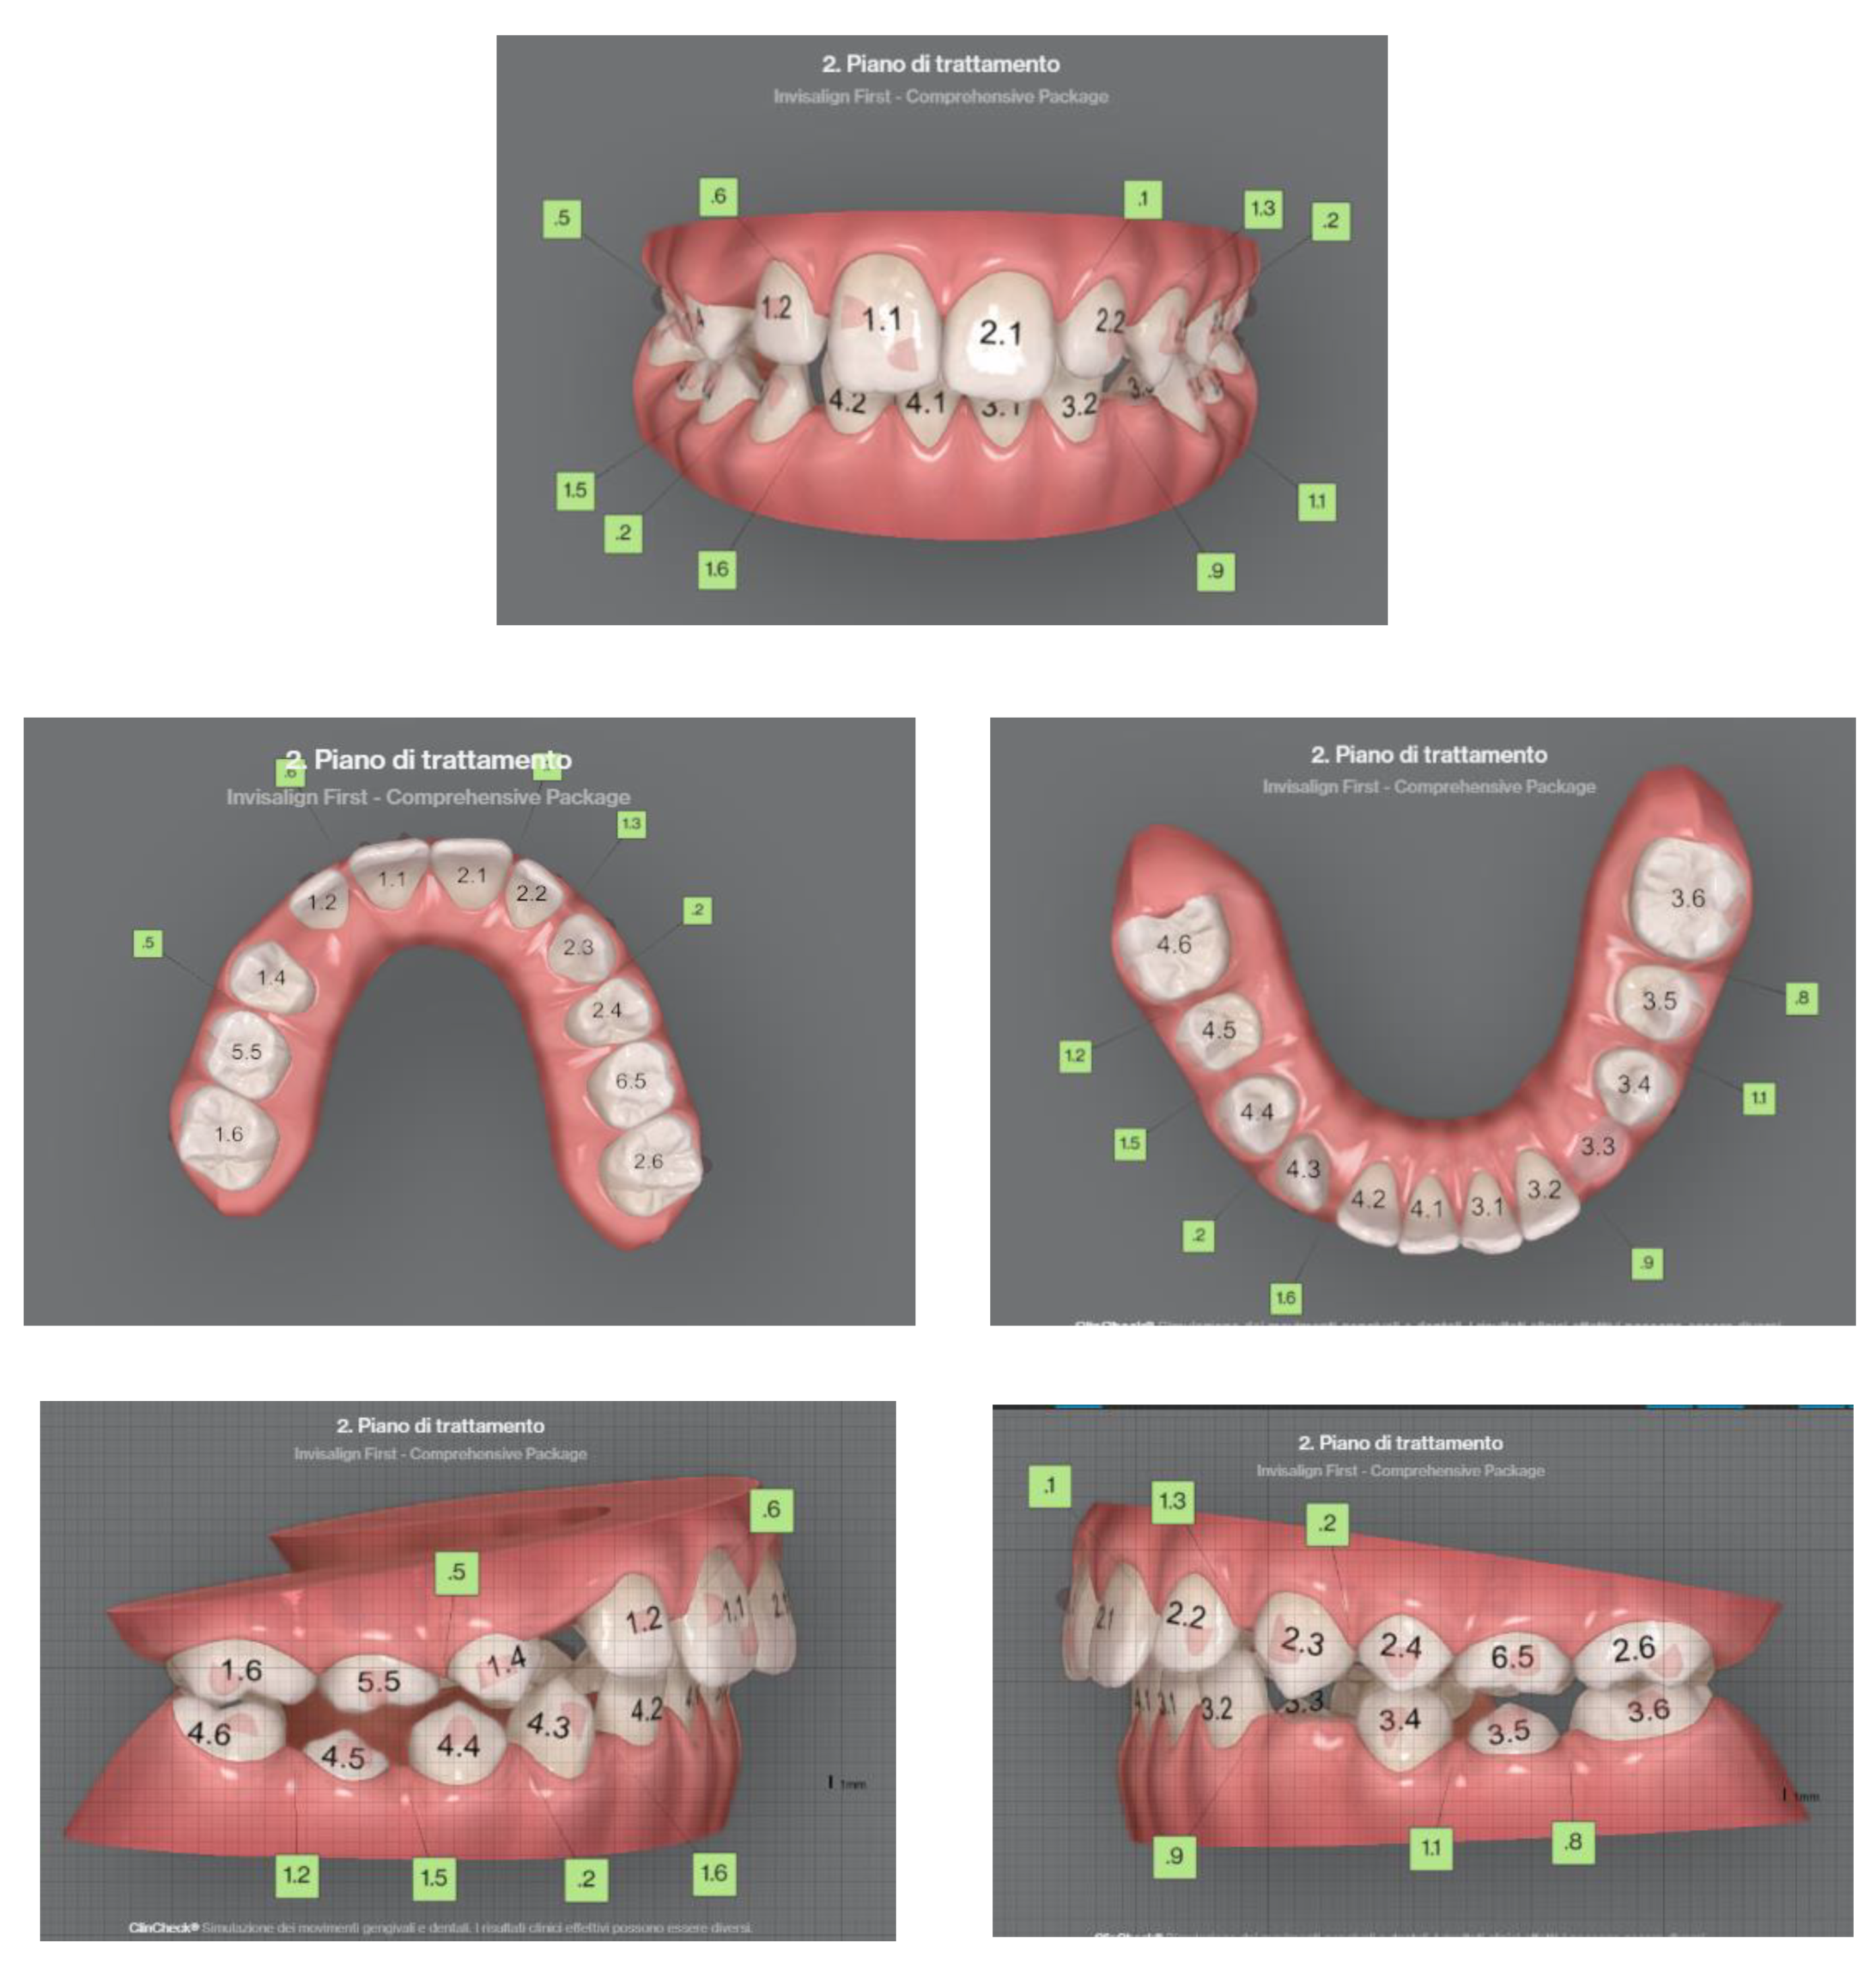

The patient is an 11-year-old female, in late mixed dentition. Clinical examination revealed acceptable oral hygiene, absence of functional anomalies and oral habits, the presence of deciduous molars (5.5 and 6.5), and erupting permanent teeth. The intraoral examination showed a molar and canine Angle class II on both sides, increased overjet, posterior unilateral functional crossbite on the right side, lower/upper midline deviated to the right/left of 2 mm, and increased overbite (5 mm) (Figure 6). The most important problem was that 1.3 was not in the arch, while the contralateral 2.3 had been present for more than 6 months. Diagnostic X-ray confirmed the 1.3 eruption delay. (Figure 7).

Figure 6. Clinical case treated with Invisalign© aligners. Intraoral views from ClinCheck. Frontal, upper, and lower occlusal and lateral view of occlusion before the beginning of treatment.